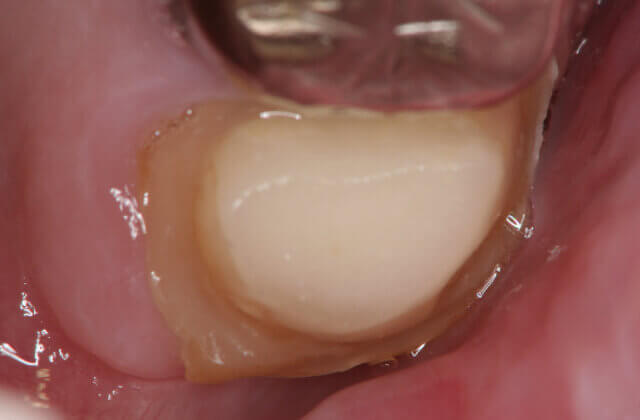

被せ物をした歯の違和感により来院されました